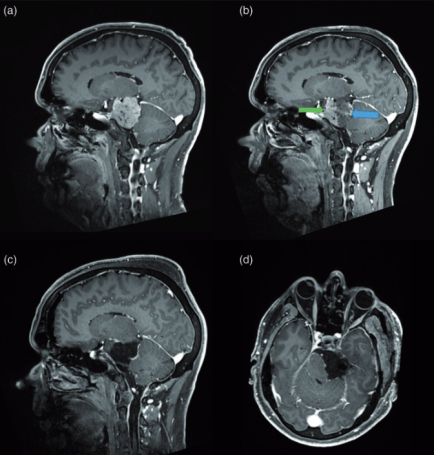

法国一位53岁男性,因三叉神经痛合并三叉神经感觉减退,在当地神经外科医院Lariboisiere医院,查出左侧较大岩斜脑膜瘤(27立方厘米)。脑磁共振(mri)显示从幕部可见明显的轴外肿瘤,岩斜向外扩张,对脑干有明显的质量效应(图1(a)),无瘤周水肿。

较终对于Sebastien Froelich教授的治疗方案,患者在手术前获得书面知情同意。Sebastien Froelich教授采取在患者全身麻醉下进行脑血管造影。传统的2Dangiography显示左侧颈内动脉虹吸管垂直部分不明显的肿瘤脸红(图2(a))。其他脑动脉注射后未见肿瘤性脸红。此外,肿瘤周围动脉有明显的肿块效应,主要表现在左侧pca和SCA上(图2(b), (c))。3d - digital减影血管造影(DSA)双视旋转序列10s,分别在左侧椎动脉注射碘造影剂和不注射碘造影剂,通过PCA和SCA更好地了解肿瘤的解剖关系。该采集允许诊断来自SCA的MTA,并为肿瘤提供丰富的动脉瘤内网络(图2(d)、(e)、(f))。这是通过选择性导管插入该动脉(Magic 1.2 FM, Balt)及其选择性血管造影证实的(图2(c))。因为这条动脉来自于硬膜内动脉,而硬膜内动脉位于手术入路的另一侧,在肿瘤的后面,所以在手术中对它的控制是困难和危险的。Sebastien Froelich教授经过与神经外科团队的讨论,决定在术前进行栓塞。用1毫升氰基丙烯酸酯胶(Glubran,Glubran -2, GEM, Viareggio, Italy)混合溶液(4ml of lipiodol)堵塞供血动脉,造影结果良好,无并发症。术后脑MR显示脑膜瘤部分断流,无脑水肿(图1(b))。除了新出现的头痛外,临床检查在血管内手术后没有改变。

手术安排在二天(图1(c),(d))。以颧根为中心的颞部开颅术和前岩部切除术。脑膜瘤在肿瘤消退的不同阶段交替进行超声抽吸和周围结构的仔细解剖,从血管的角度观察,硬脑膜边缘被切断以完成肿瘤的断流。肿瘤的上半部分是完全无血管的。下腔静脉仍被SCA的硬脑膜幕动脉近端血管化。切除是完全的,除了一小层脑膜瘤,它是沿着SCA留下的,因为它被发现与血管较为相异,不能在不牺牲SCA的情况下切除。全部周围的颅神经IV、V、VII、VIII和VI均保存完好,患者术后神经功能完好。